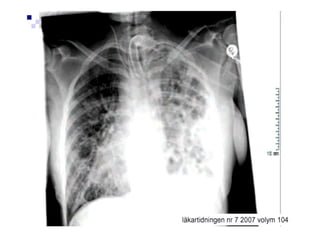

Übertragung : • überZecken direkt • Kot befallener Haustiere • intrazelluläre Erreger Klinik: • starke Kopfschmerzen (Gehirn) • Fleckfieber , hohes Fieber. • Arthralgien(stechende Gelenkschmerzen) • Bradyarrythmien (Herz) , Endocarditis • Lungeninfiltrate (atypische rez. Pneumonien) • seltene, schlecht heilende Hautabszesse Diagnostik : • KBR (rel. einfache Komplementbindungsreaktion) • Weil-Felix-Reaktion (verstärkt) Therapie: • Doxy 200 mg für 3-7 Tage • Acithromycin 500mg/die • ggf mit Rifambicin 100mg-600 mg/die

Erkrankungen des Lymphsystems: 1)Erysipel: Rötung und Schwellung der Unterhaut. und tiefere Schichten bakterieller Befall mit Beta-hämolysierenden Strptokokken, Eintrittspforten Haut, Therapie: Unacid 3x 3 g iv. Bei nekrotisieirender Faszikulitis: Leukos , TNF, BSG und Penicillinallergie -> Ausweichen auf Klacid iv.oder Erythromicin iv.zusätzlich NSAR und Behandlung der Begleiterkrankungen. 2) Lymphödem : strangartige Rötung der Lymphgefäße 10% hereditär, 85 % durch Infekt oder TU, ggf. Lympgdrainagen Therapie z.B. Sobelin . 3) Lymphangitis: Entzündung von Benachbartem Gewebe: Abstrich und Antibiose z.B Staphenor oder Sobelin iv. 4) Phlegmone: oberflächliche Entzündung der Haut z.B durch Phlebitis etc. 5)Abszeß tiefergehend abgekapselt , häufig von Haarbalg ausgehend. Furunkel-Karbunkel-Abszeß.